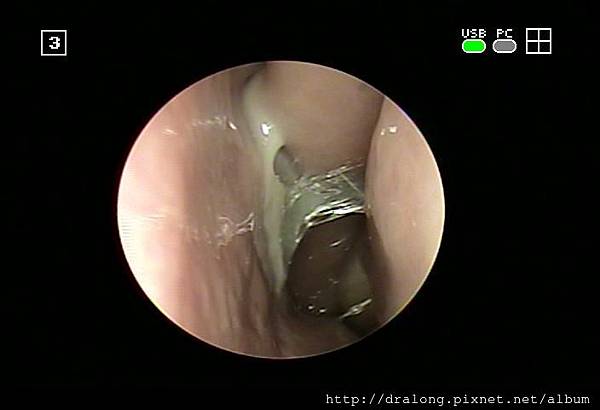

50多歲中年婦女,感冒之後雖然有在外院接受治療,可是一直沒有痊癒,且已經超過兩個星期。症狀是膿鼻涕,頭痛,咳嗽有痰,且胸口會悶痛,晚上不好睡。雖然沒有發燒,沒有其他併發症,可是症狀嚴重干擾影響生活。除了常規的局部治療及給予常用抗生素外,幫她做了細菌培養,沒想到長出的細菌不是鼻竇炎常見的細菌Streptococcus pneumonia(肺炎鏈球菌),H.influenza(流行性嗜血桿菌)或M.catarrhalis(卡他莫拉菌)。而是Serratia marcescens格蘭氏陰性桿菌,常見於土壤及水中。通常此菌感染於老年、長期住院和多種抗生素治療者。另一種則是Methicillin -resistant-staphylococcus aureus (MRSA)金黃色葡萄球菌抗藥菌種。此時只好依照細菌培養結果給予特殊抗生素治療才有效了。雖然病人沒有其他的慢性疾病或服用免疫抑制藥物,但因為病人服藥順從性不好,很可能因此而讓細菌產生抗藥性。特別囑咐病人要按時服藥,且要回診治療痊癒才能停藥。經過2星期的抗生素藥物治療加上徹底的鼻子局部治療,總算將難纏的鼻竇炎治癒。

急性鼻竇炎常見原因是因為急性上呼吸道感染(感冒)而引起的次發性細菌感染所造成,少數則是因上排牙齒蛀牙感染引起。當有鼻子過敏,鼻中隔彎曲,鼻內異物,腫瘤,鼻息肉,或過度使用解鼻塞噴劑(像歐X鼻),就更容易會造成鼻竇炎。所以只要有感冒就別忘了會有鼻竇炎的風險。鼻竇炎的主要症狀有鼻塞、流膿鼻涕、頭痛、眼睛或臉頰漲痛、嗅覺變差、鼻水倒流、咳嗽(可咳出膿痰)等症狀,更常使人頭昏昏沈沈,注意力難以集中、情緒低落、記憶力減退,影響工作,睡眠和生活。而小孩子更容易因為鼻竇炎而讓中耳炎,咳嗽拖了好幾個禮拜都沒明顯改善。更嚴重者會產生鼻竇周圍骨髓炎,頑治性中耳炎,眼窩蜂窩組織炎、海綿竇栓塞及嚴重腦膜炎和腦膿瘍等併發症。鼻竇炎的致病菌是一般常見的上呼道內的細菌包括肺炎雙球菌、嗜血性流行性感冒桿菌、卡他莫拉菌等。所以在治療上主要是選擇對上述細菌有效的抗生素,使用正確的劑量及完整的治療時間,才能成功達到治癒疾病。急性鼻竇炎的用藥時間需要1~2週,慢性鼻竇炎則會更久(4~6週)。要是慢性鼻竇炎藥物治療效果不好,有時候須搭配生理食鹽水清洗鼻子,甚至需要更進一步接受手術的治療。所以要是感冒歷久不癒時,最好立即診治,以免由急性鼻炎發展成為及性鼻竇炎,甚至變成慢性鼻竇炎可就麻煩了。